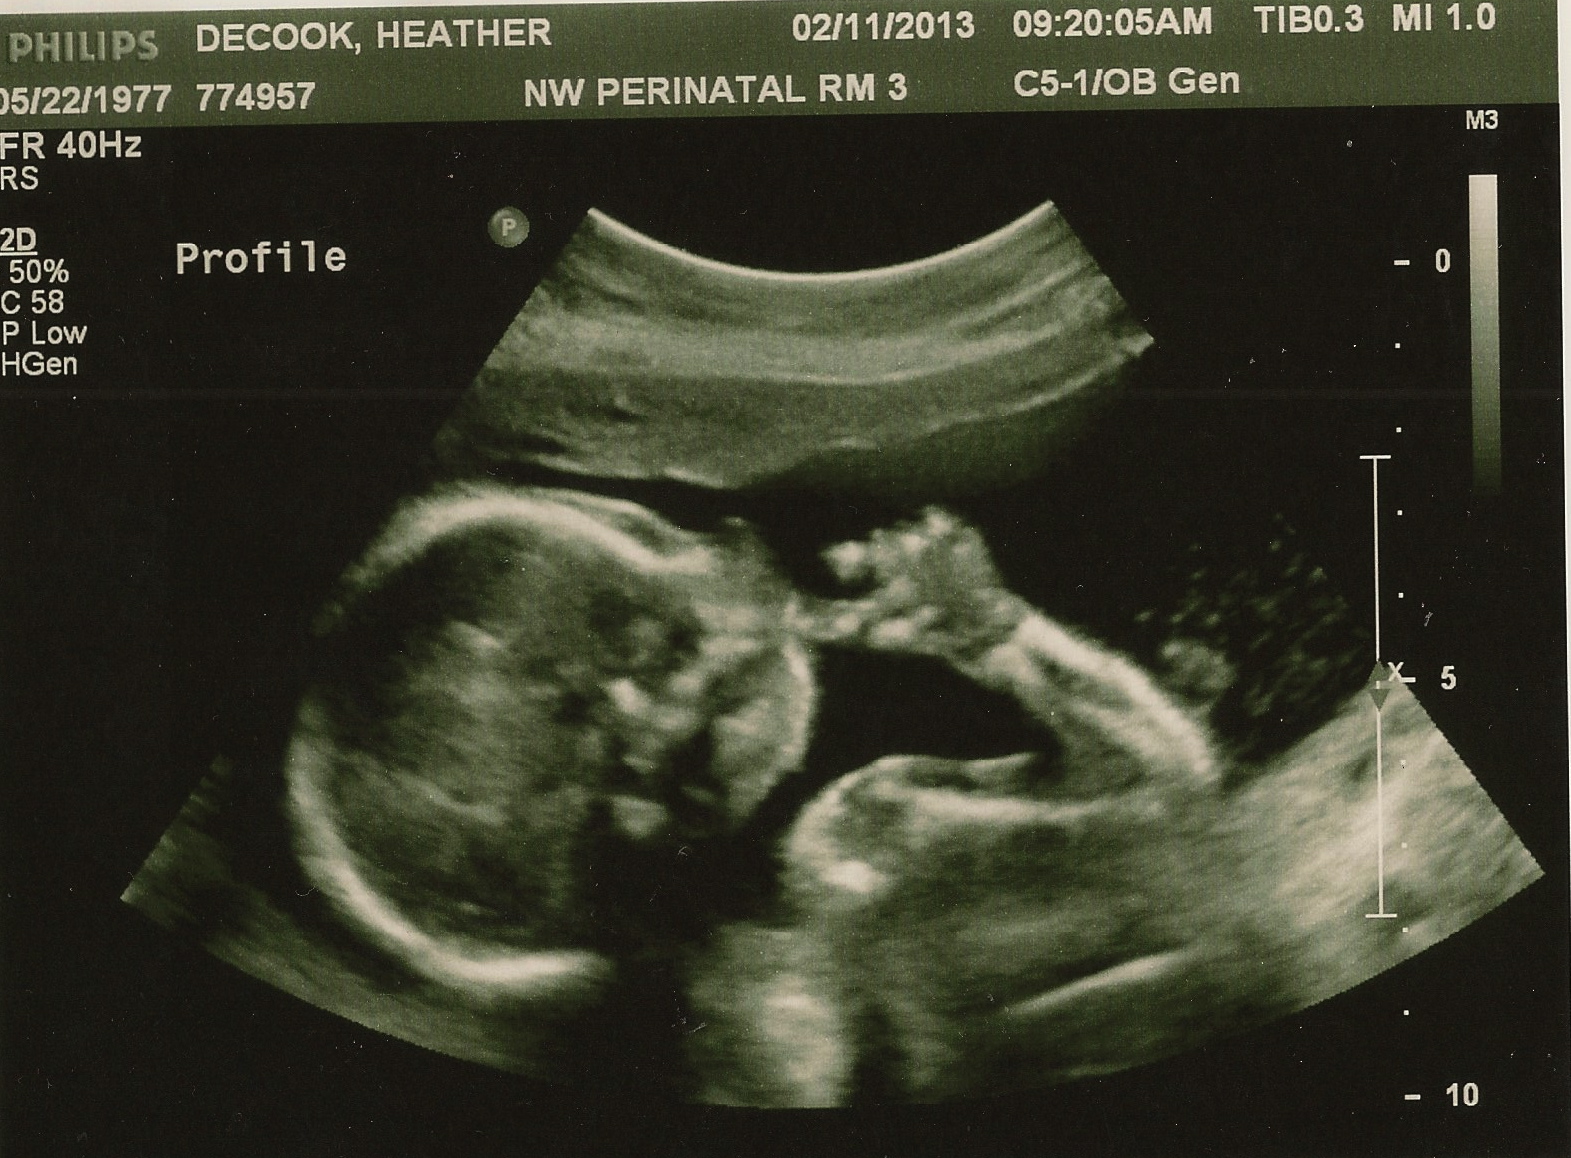

| He managed to get his little thumb into his mouth while we were watching. You could actually see his little mouth sucking on it. |

| His sweet little profile. |